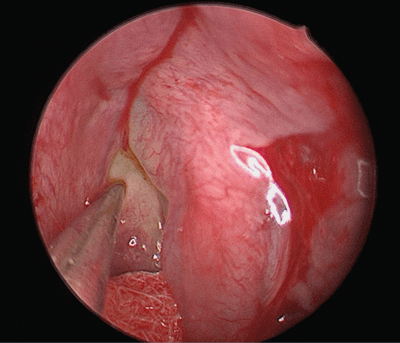

Combinations of 0 and 30-degree endoscopes are used. The area of the defect which was identified from the cross-sectional imaging is approached with the endoscope to examine for any visible fluorescein mixed CSF leak. This can be easily identified due to its colour and pulsatility (see Figure 1). This area is confirmed with the Brainlab probe.

Figure 1. Fluorescein mixed CSF leak on the ethmoidal bullae.